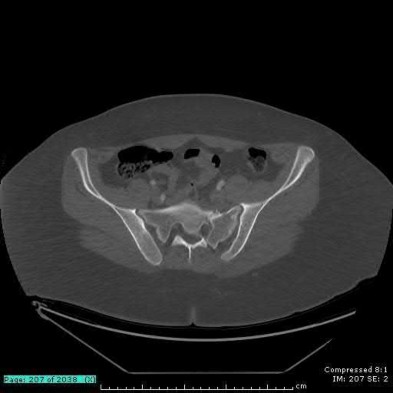

A 35 year-old female presents after prolonged extrication from a motor vehicle collision complaining of severe pelvic pain. Physical examination reveals diminished perianal sensation. She is otherwise neurologically intact. Figures A through D are radiographs and representative CT cuts of her injury. Which of the following nerve roots has likely been injured by the acute trauma?

The clinical scenario is consistent with a high-energy sacral fracture. The radiographs in figures A and B demonstrate a sacral fracture with posterior displacement of the right hemipelvis seen on the inlet view. Figures C and D are axial and sagittal CT images which show a displaced fracture of the right

hemisacrum along with a transvere fracture component through the S3 body . Diminished perianal sensation is concerning for an S2 nerve root injury.

Mehta et al reviewed the current management of sacral fractures. They note that the S1 and S2 nerve roots are more likely to be injured with sacral fractures as they occupy 1/3 to 1/4 of the neural foramina, as opposed to S3 and S4, which only occupy 1/6 of the neural foramina.

Robles reviewed the current literature to ascertain principles of evaluation and treatment for transverse sacral fractures. The author notes that injury to nerve roots S2 to S5 is manifested by impairment of urinary and anal continence and sexual function.